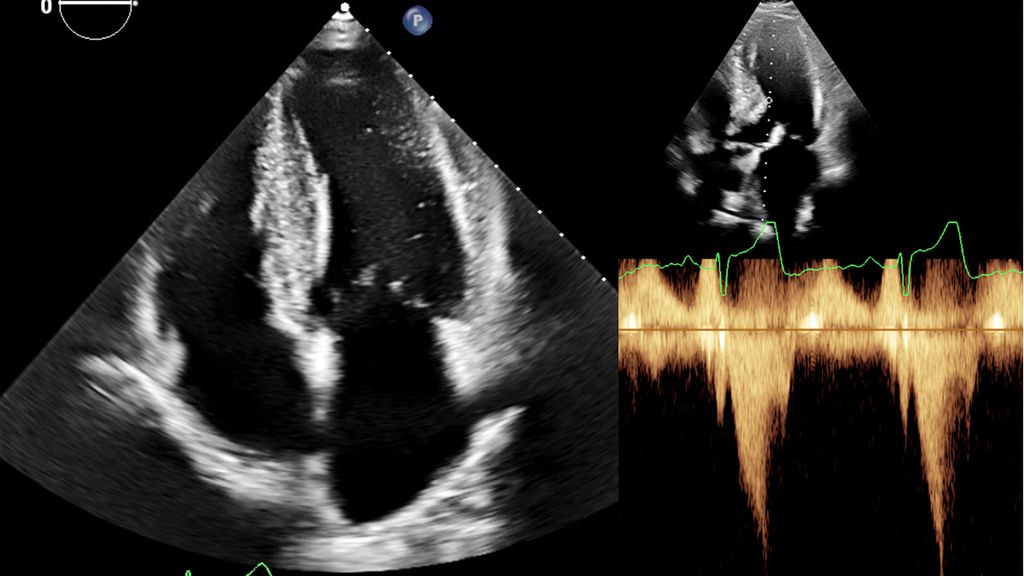

Abb. 2: Echokardiografie bei HOCM mit 4-Kammer-Blick (links) und Obstruktion im Ausflusstrakt (rechts)

Dennoch ist die Echokardiografie aufgrund der niederschwelligen Verfügbarkeit als erste Untersuchungsmodalität und zur Verlaufsbeurteilung nicht wegzudenken. Mit der Ejektionsfraktion, der Vorhofgröße und der Beurteilung der diastolischen Funktion können prognostisch wichtige Parameter erhoben werden. Ein „apical sparing“ in der Analyse des myokardialen Strains oder der Aspekt eines „granular sparkling“ kann einen Verdacht auf kardiale Amyloidose begründen (Abb.3). Jede echokardiografische Untersuchung wegen des Verdachts auf LVH sollte außerdem eine Bestimmung des LVOT-Gradienten inkl. Valsalva-Manöver beinhalten (Abb.2).